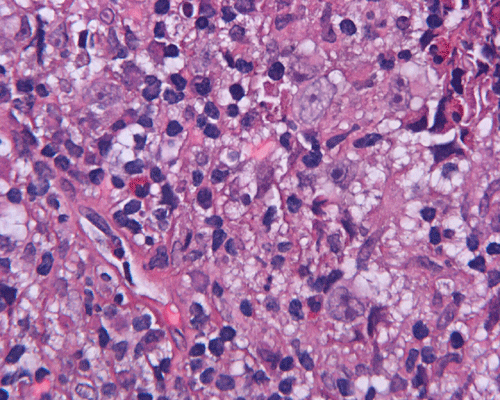

Paraffin sections: The entire volume of the tissue is made up of a granulomatous inflammation with poorly formed granuloma (Panel F, G, and H). The density of the lymphocytes is variable in different areas. In some areas, there is a rather intense lymphocytic infiltration accompanied by scant atypical cells with enlarged nulcei and prominent nucleoli (arrows in Panel I and J, Panel J is a higher magnification of Panel I). These atypical cells are quite easy to be missed. No microorganisms were identified by acid fast stain, PAS stain or GMS stain. The lymphocytes but not the atypical cells are positive for CD20 (Panel K) or CD3 (Panel L). The granulomatous background is strongly positive for CD68 (Panel M). Only rather faint positive staining for placental alkaline phosphatase (PLAP) is demonstrated and the interpretation is difficult as they are present in areas with crush artifact (Panel N). Many of the large, atypical cells are positive for CD117 (c-kit) (Panel O).

Intracranial germinoma is histologically identical to ovarian dysgerminoma and testicular seminoma. There is a tendency to infiltrate adjacent structures and to spread throughout the ependyma, the ventricular system and subarachnoid spaces. Microscopically, they consist of nests, lobules, cords, and/or sheets of large round tumor cells with well-defined borders, clear to pale cytoplasm with artifactual vacuolization, round and centrally located nuclei with open chromatin and prominent round or bar-shaped nucleoli. The cytoplasm is glycogen-rich, making these cells periodic acid-Schiff (PAS)–positive and diastase sensitive. These tumor cells are mitotically active. Atypical mitosis, however, is not a common finding. Necrosis is usually not prominent.  In the most classic histologic picture, clusters and cords of large germinoma cells are separated by a dense, lymphocytic infiltration admixed with some macrophages and a delicate fibrovascular network. Plasma cells may be found. At medium-power magnification with hematoxylin and eosin stain, the contrast between the smaller, darkly staining lymphocytes and the larger, pale staining cytoplasm of neoplastic cells is virtually pathognomonic. The amount of inflammatory cells can have wide variations among different tumors. In some occasions, the large germinoma cells are difficult to be found and the overall picture may suggest a lymphoma. Syncytiotrophoblastic cells can also be present. These cells should not be mistaken as evidence of choriocarcarcinoma.

Germinomas can elicit an atypical gliosis in the surrounding glial tissue which may be confused with malignant glial neoplasms. This is true particularly of specimens taken from the periphery of the germinoma. The tumor may appear as a desmoplastic tumor. The inflammatory response may be problematic in reaching a histologic diagnosis, especially in small biopsies, as macrophages can be difficult to distinguish from a non-seminomatous neoplastic component.

Granulomatous changes are common findings in germinomas and intracranial germinomas follow this general trend 3, 4, 5. It can be extensive. This feature is particularly problematic in neuropathologic when stereotactic biopsy is performed and the amount of tissue available for examination is limited as illustrated in this case. During intraoperative consultations, a frozen section diagnosis of granulomatous inflammation should prompt additional sampling as isolated granulomatous inflammation of infectious origin and sarcodosis are quite uncommon in the pineal gland.